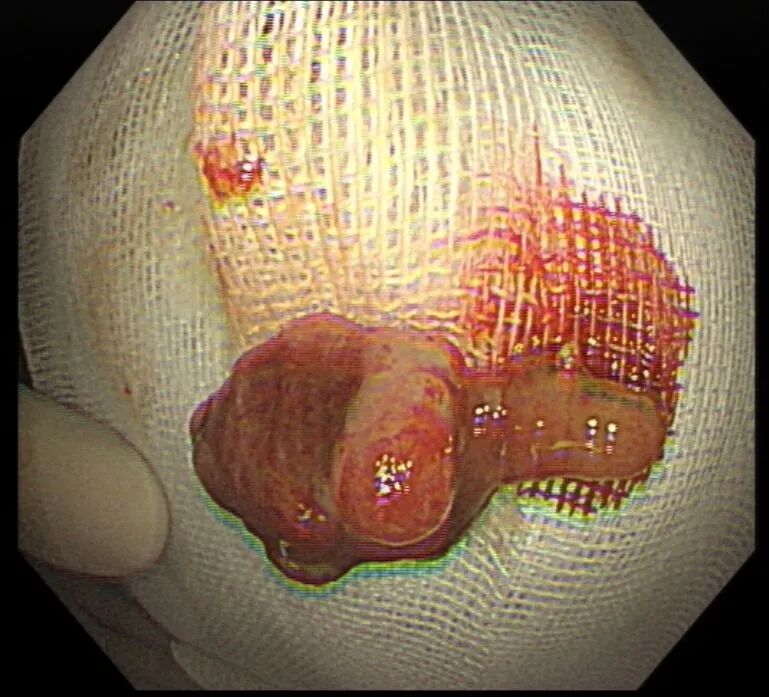

考虑到息肉体积大、蒂部粗壮,内部极可能存在粗大的滋养血管,直接切除极易引发术中、术后出血,徐思楠医生当机立断,在和小金妈妈充分沟通、取得书面知情同意后,当场为小金制定了缜密的手术方案,在手术过程中,徐医生先用数枚钛夹精准夹闭息肉的粗蒂根部,彻底阻断息肉的血液供应,再用圈套器完整套住息肉头部,通过规范的电凝电切操作将息肉完整切除,最后再用钛夹严密封闭手术创面,全程几乎无明显出血,操作顺利完成。术后,小金转入住院部,接受了规范的禁食、静脉补液、营养支持等治疗,未出现出血、穿孔等并发症,很快恢复了正常饮食,顺利康复出院。术后病理结果最终揭晓,这枚息肉为幼年性息肉,属于良性病变,后续只需定期复查肠镜即可。